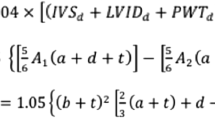

Using the procedures described in methods, the final best fitting model to estimate normative values for each of the CMR-based volumetric parameters focused on BSA as the key metric:

A z-score calculator is provided to reflect the deviation of patient’s measured volume from the norm estimated from the model using the following computation: